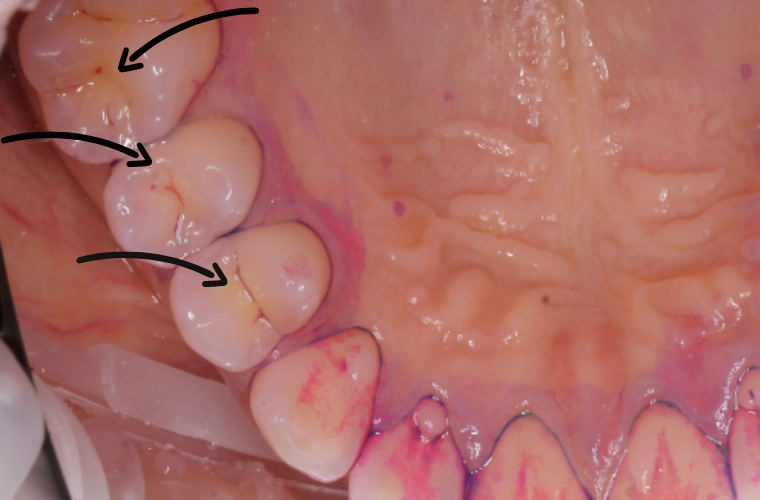

Фиссуры зубов (пациенту проведено окрашивание индикатором зубного налёта  перед сеансом профессиональной чистки зубов)